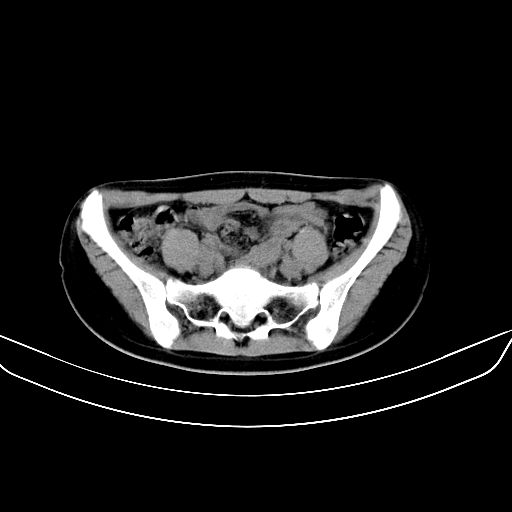

以下是引用zsl6918在2008-7-11 21:40:00的发言:[br]双侧骶髂关节骨质破坏以下三分之一为主,符合强直性脊柱炎表现

以下是引用zhangzhongshou在2008-7-11 21:41:00的发言:[br]患者是女性,hla-b27抗原(—),首先不太考虑强直性脊柱炎,建议查类风湿因子,骶髂关节改变考虑类风湿性关节炎可能性大,建议进一步检查。